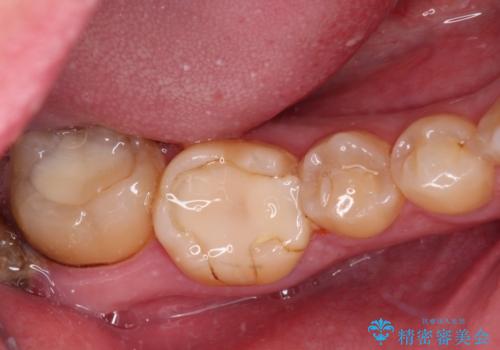

- 左右下顎の奥歯に違和感を感じるとのことで来院された患者様です。

最近ものが挟まりやすくなったり、冷たいものがしみるようになったりと言った症状があり、診査したところ、歯質の欠損や不適修復物などが認められました。

精度の高いセラミックインレーによる修復治療が第一選択となりますが、一方の歯は元々修復物が大きく、咬合力の強い方であったので、セラミッククラウンによる補綴治療を行うこととしました。